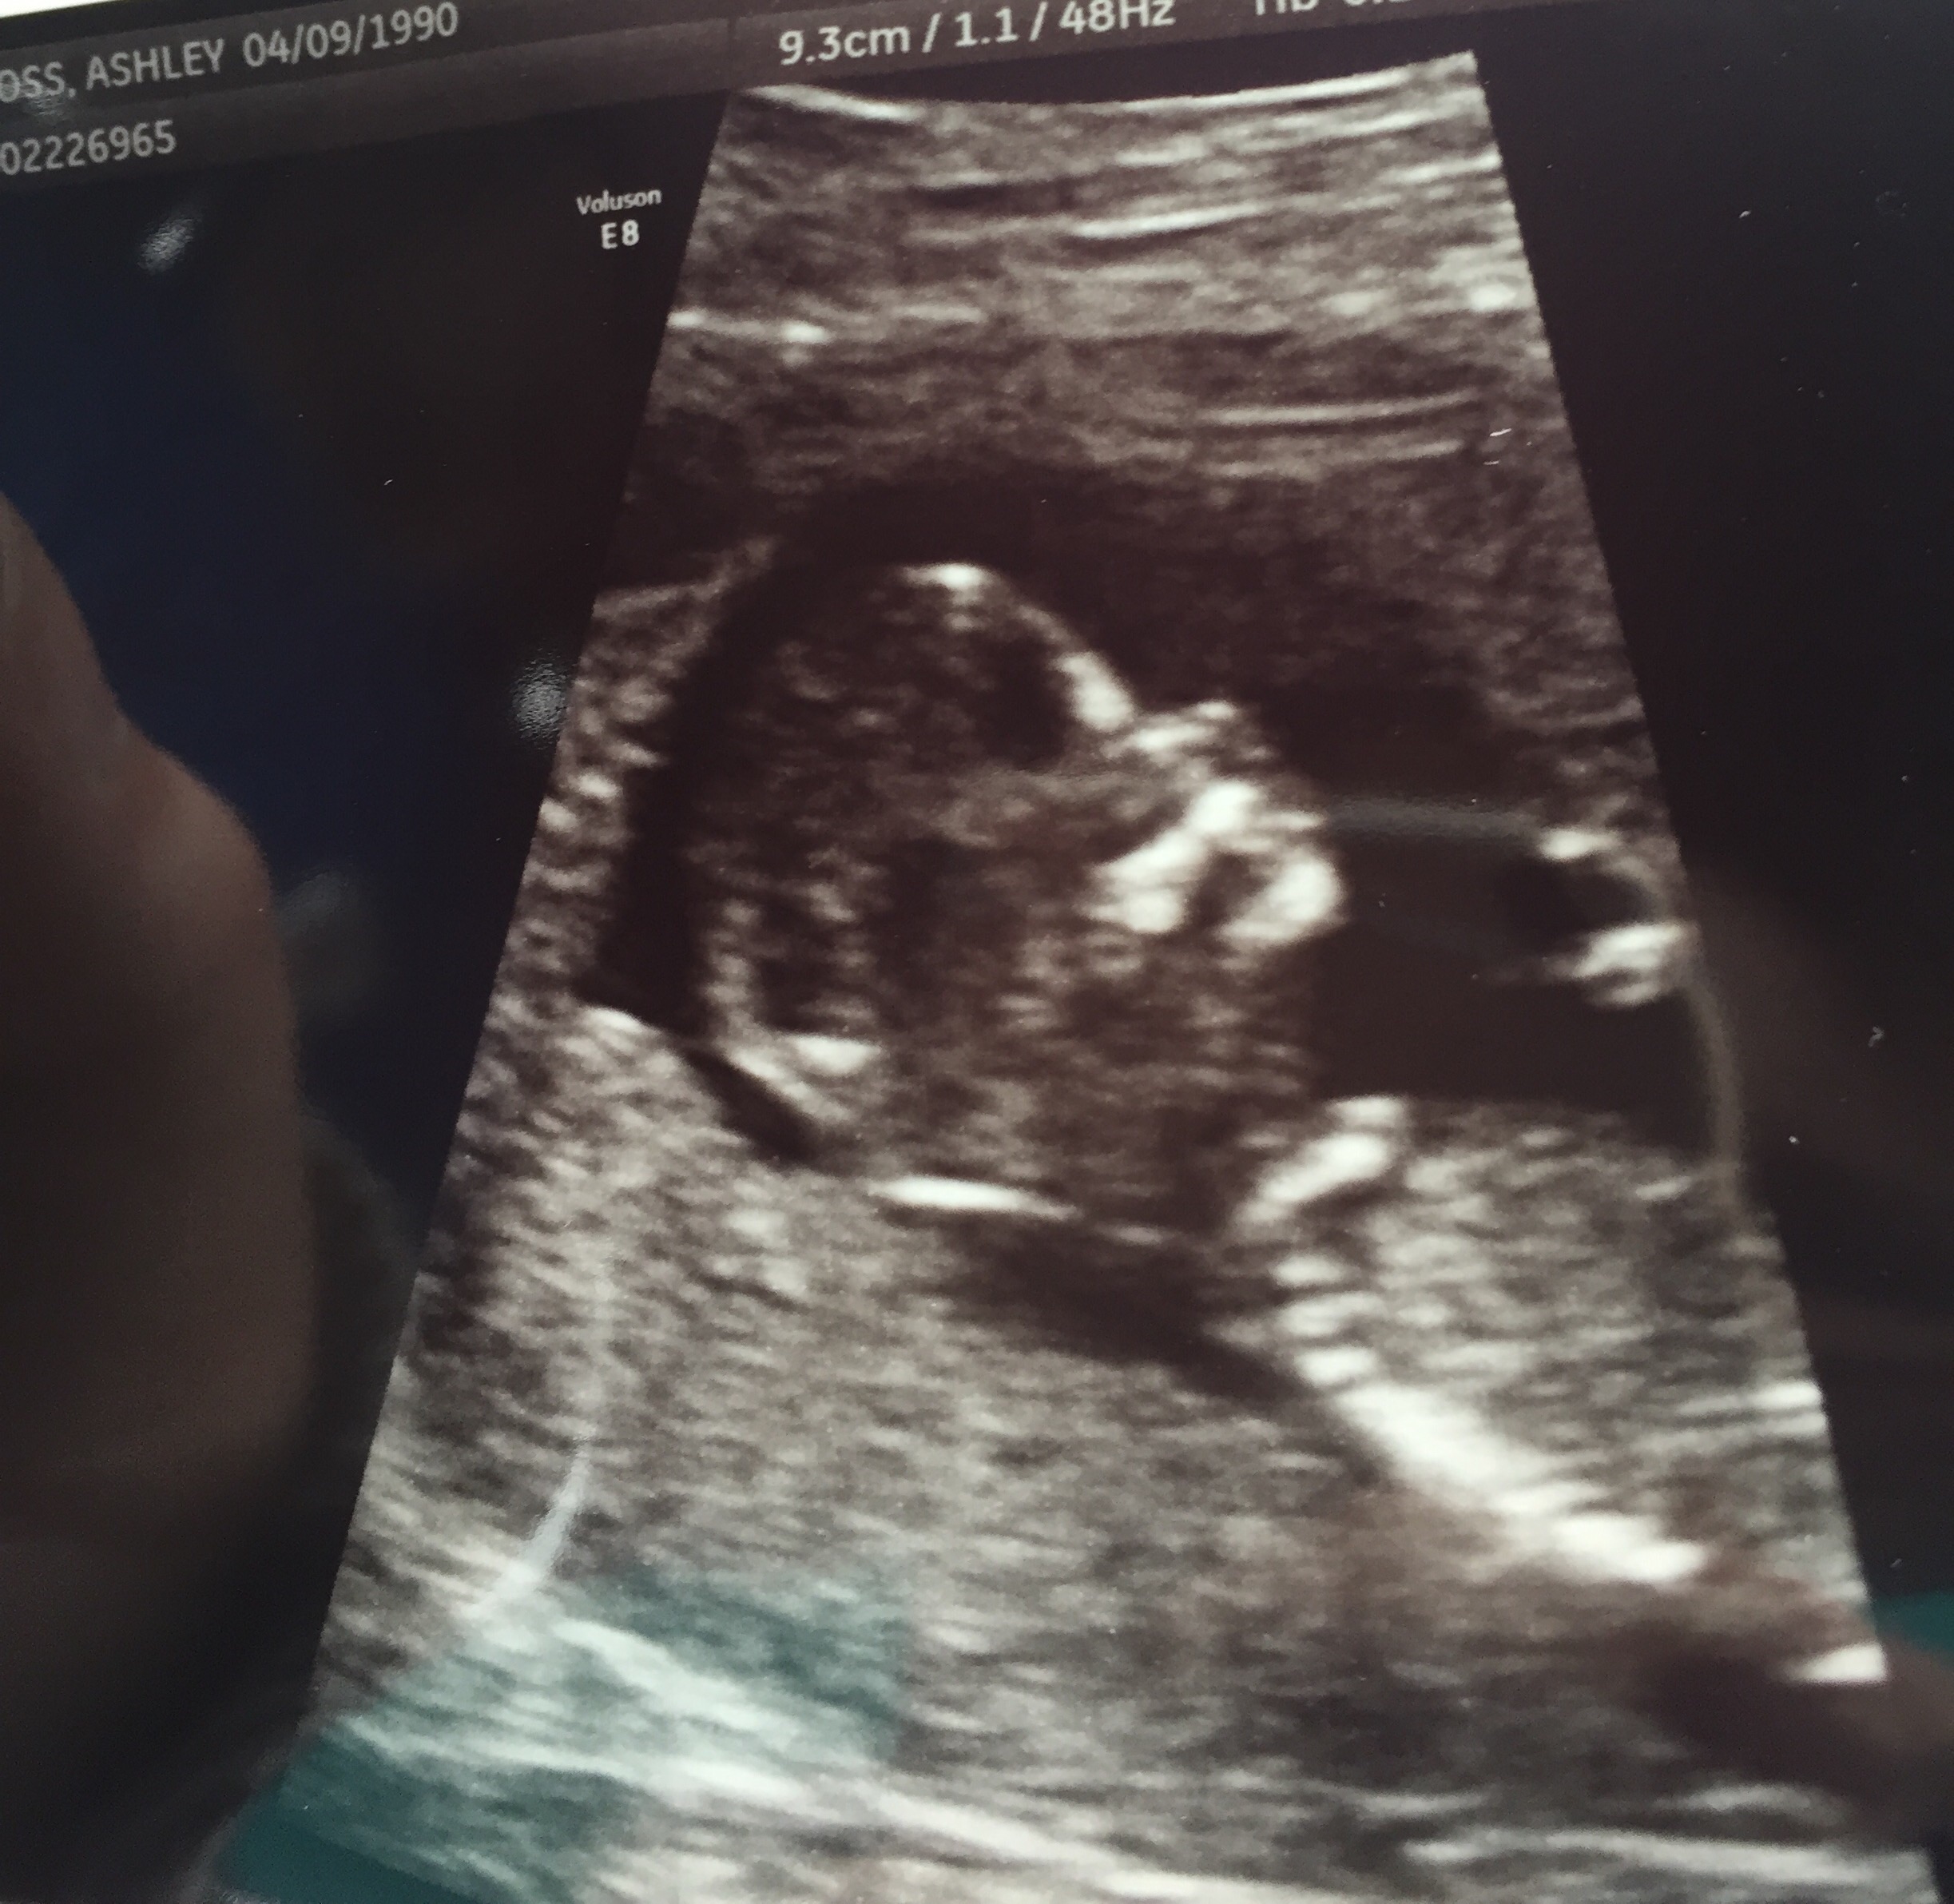

14 weeks, 1 day. I had an abdominal u/s. I've decided to call it my little wiggle worm because it wouldn't stop moving around, and stretching! It took three tries for the tech to capture the heartbeat (148). At one point she managed to get positioned just right to see it's entire front, and not even a second later, it completely turned itself around